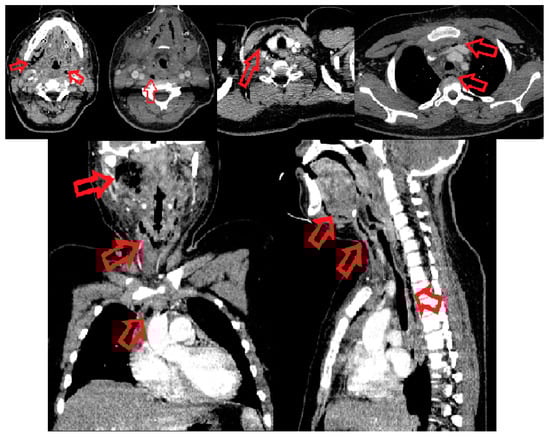

The contrast-enhanced CT scan of head, neck and thorax revealed multiple mixed fluid-air densities in the infratemporal, sublingual, submandibular, submental, parapharyngeal, retropharyngeal and peripharyngeal spaces and extended to the mediastinal level, on the upper and middle floors of the anterior and posterior compartment; it also revealed edematous infiltration of perimandibular, submandibular and laterocervical subcutaneous bilateral soft tissues (Figure 1).

Figure 1. CT scan. The red arrows point to the necrotic and gaseous collections in the affected areas—infratemporal, sublingual, submandibular, submental, parapharyngeal, retropharyngeal and peripharyngeal spaces, and extend to the anterior upper mediastinum.